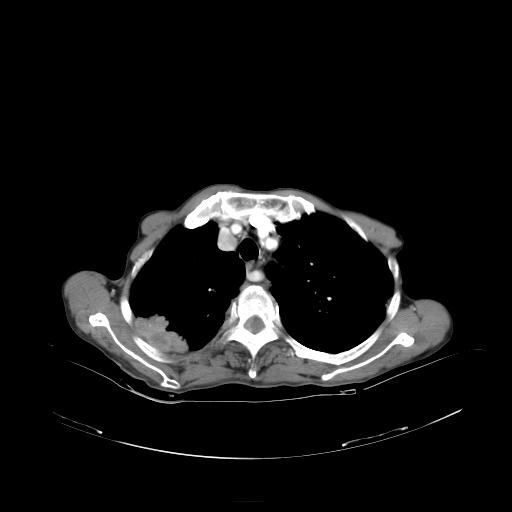

女,72岁,咳嗽一周余,突发右下肢无力二天。

pe:bp-140、80mmhg,精神可,伸舌居中,右上肢肌力正常,右下肢肌力0级,巴氏征+

来院做头颅+胸部ct平扫

遂加作增强:

胸部病变平扫35hu,增强强化至70hu

这个病人首先是胸部病变的定位到底是肺内还是肺外。仔细观察块影位于胸膜下,与胸膜间有透亮带,且近端血管未见明显推移而是引流样改变,形态分叶,说明这个病灶位于肺内胸膜下。很可能是腺癌,腺癌最易致颅内高密度转移灶。局部胸膜有侵犯。

本例颅内见多发大小不等高密度灶,有强化及水肿;另外,胸锁关节层面可能是第四胸椎及右侧肋骨起始部骨质欠连续,椎旁软组织肿胀,建议调骨窗观察。

诊断:右下肺癌伴颅内、胸椎、肋骨转移可能性最大。